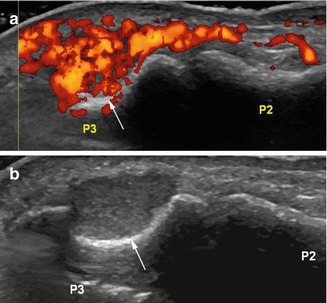

Glomus tumor of the nail bed. (a) Ultrasound. (b) Power Doppler image. (a) Ultrasound images show an isoechogenic mass eroding the underlying distal phalanx (P3) (arrow). The lesion is markedly hypervascular (b) on power Doppler image